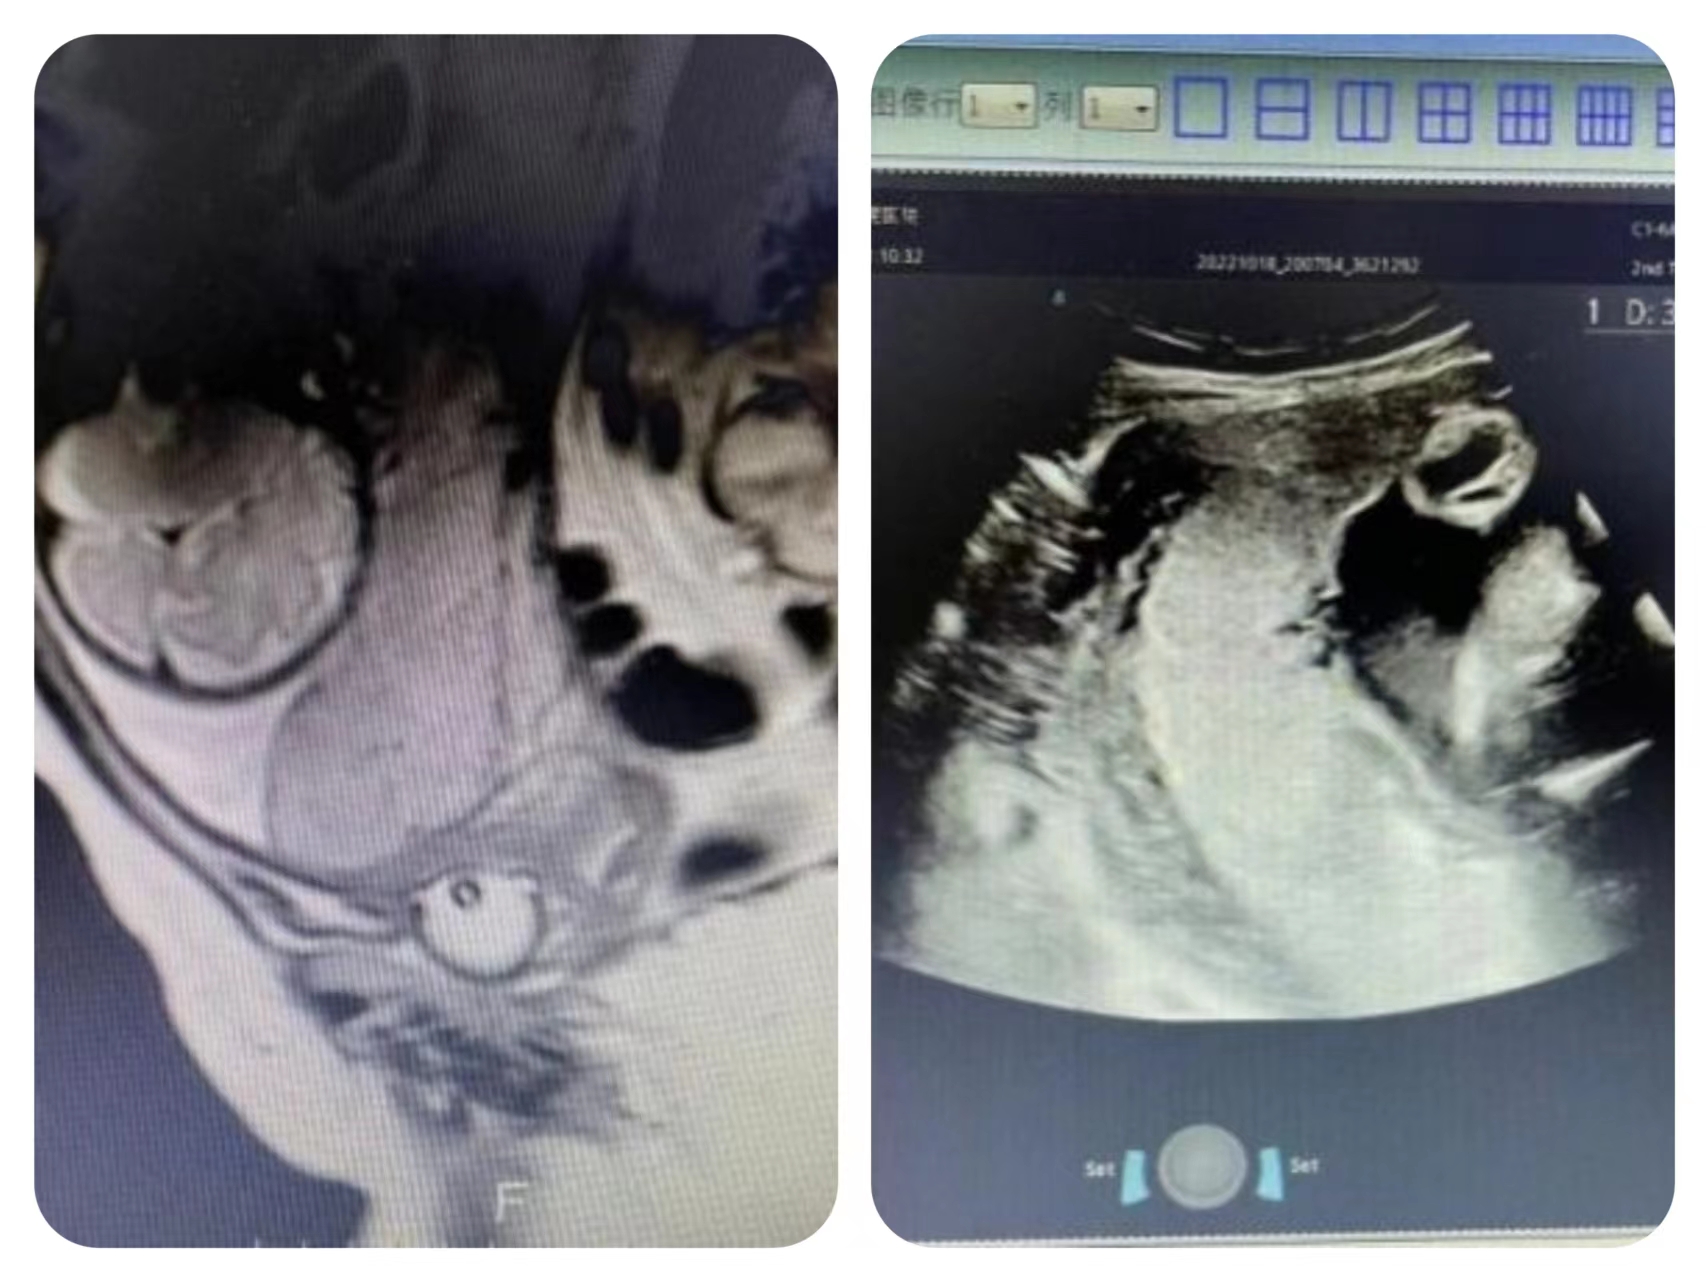

10月19日,对患者行盆腔核磁检查,结果提示:患者完全性前置胎盘,胎盘后下缘植入,膀胱底与胎盘分界不清,受侵不除外。结合彩超及盆腔MRI结果,此患者前置胎盘评分为9分,为重型胎盘植入!此时,患者经对症处理,暂无明显出血,妇产科赵爱梅主任将该患者病情上报医教部,并组织多学科会诊,进行术前讨论,充分评估风险,确定手术方案。

10月20日早六点半,值班医生李瑜查房发现患者再次阴道出血,立即向赵爱梅主任汇报病情,并通知管床医生许冰霜医生。考虑患者宫内孕35周1天,术前检查已完善,现阴道再次出血,经与患者及家属沟通后,决定手术。